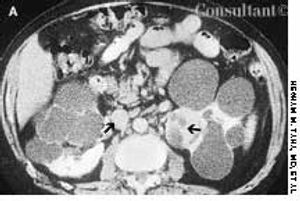

A 45-year-old man complained of blood in his urine. The patient had a 7-year history of chronic renal failure secondary to hypertension; he had undergone hemodialysis for the past 5 years.